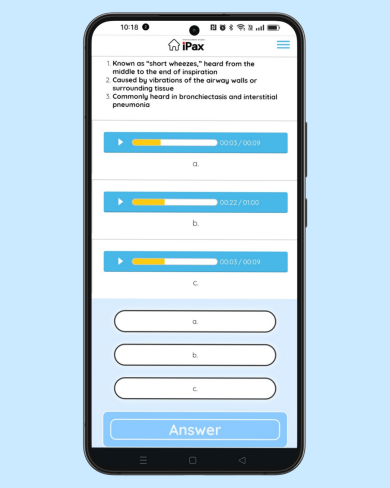

Daily quiz

2025/06/18

June 18 – Question on Crackles Today’s question focuses on crackles. The question includes a description of the characteristics of the crackling sound. Please listen to the two MP3 audio files and choose the one that matches the description. (June 18, 2025)

この記事を読む